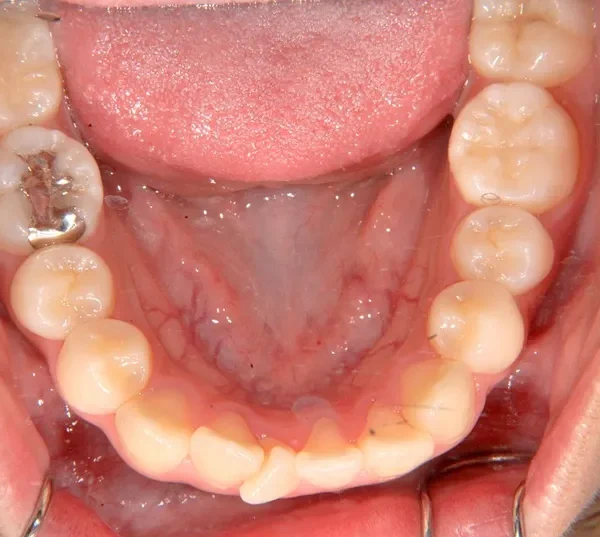

初診時年齢 中学生 (女性) 主訴 八重歯・噛めない

診断名 叢生・開咬 装置名

状態 ガタガタ・でこぼこに生えている(叢生)

八重歯(叢生)

前歯で噛めない(開咬/オープンバイト)

歯ががたがたで、噛み合わせもずれています。